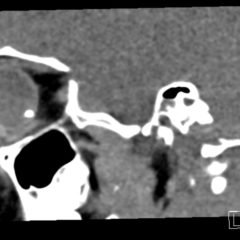

X-rays of the foot were obtained and no radiopaque foreign body was visualized. Due to high clinical suspicion for retained foreign body, a point-of-care ultrasound was performed by applying a high-frequency linear probe at the area of discomfort. In the long axis an ovoid focus of hypoechogenicity (orange outline) is visualized. Within this finding there is a linear focus (yellow line) of increased echogenicity measuring 1 mm in diameter and 1 cm in length. On short axis view, a rectangle focus (green dot) demonstrating shadowing (blue highlight) is seen.